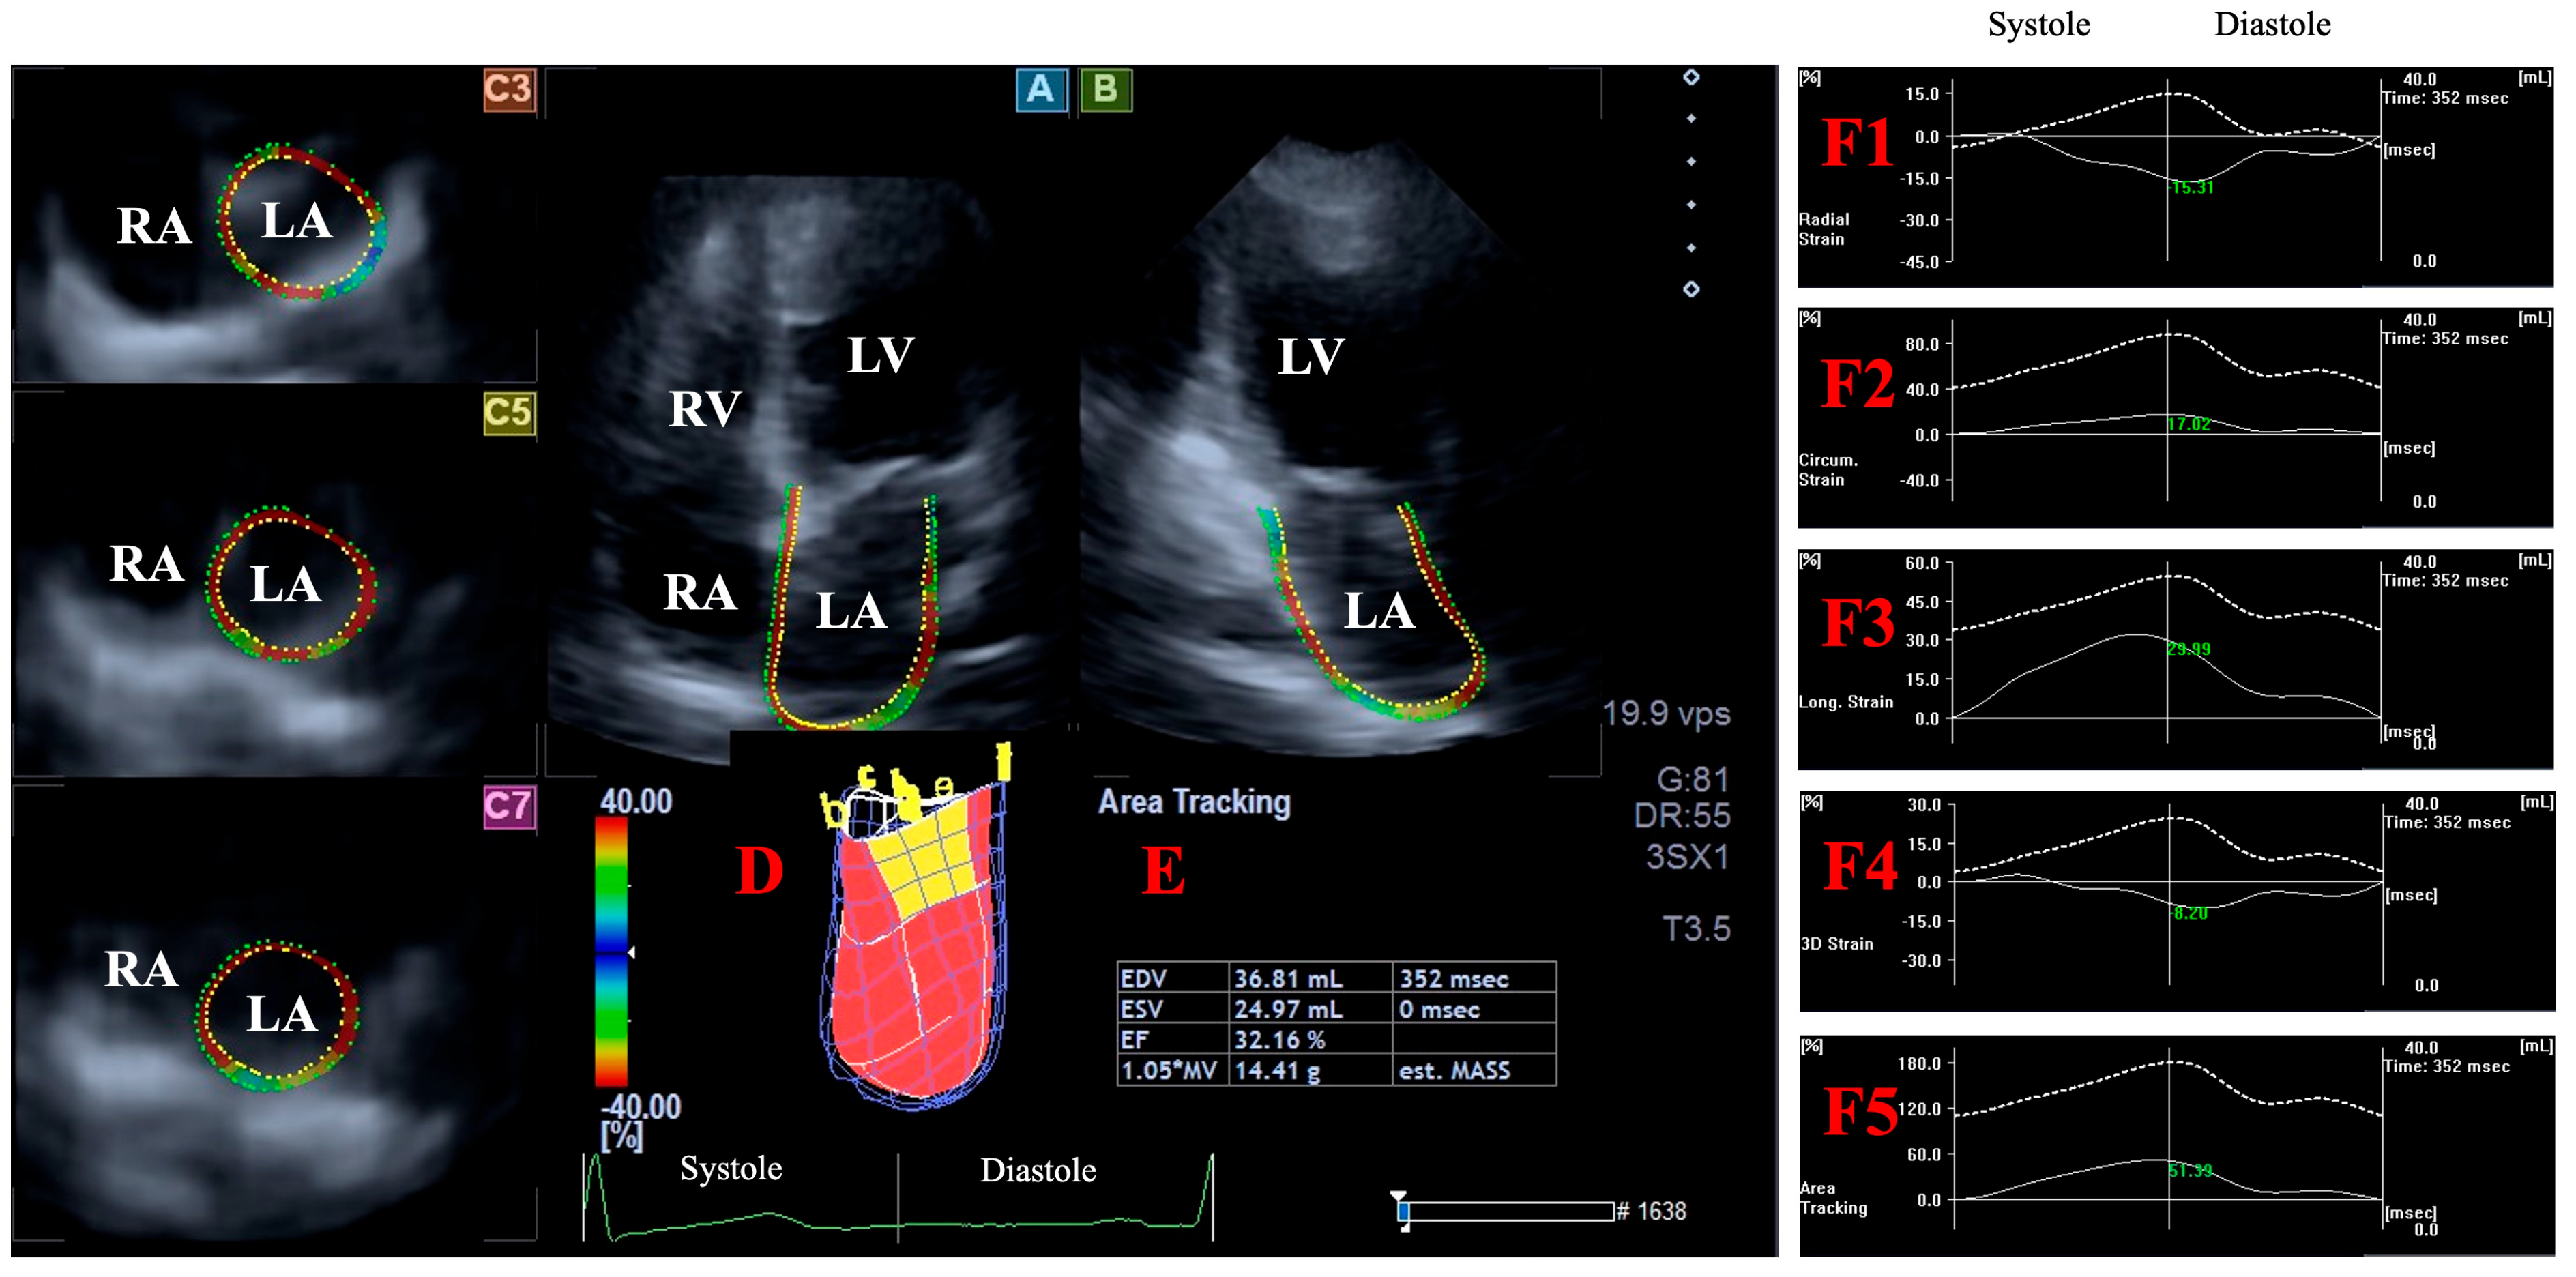

2.5. Three-Dimensional Speckle-Tracking Echocardiography-Derived Assessment of Peak LA Global Strains

- LA-Vmax—maximum LA volume at end-systole;

- LA-VpreA—pre-atrial contraction LA volume at early diastole;

- LA-Vmin—minimum LA volume at end-diastole;

- LA-GRS—LA global radial strain representing LA thinning/thickening;

- LA-GCS—LA global circumferential strain representing LA widening/narrowing;

- LA-GLS—LA global longitudinal strain representing LA lengthening/shortening;

- LA-G3DS—LA global 3D strain, combination of all unidirectional LA strains;

- LA-GAS—LA global area strain, combination of LA circumferential and longitudinal strains.